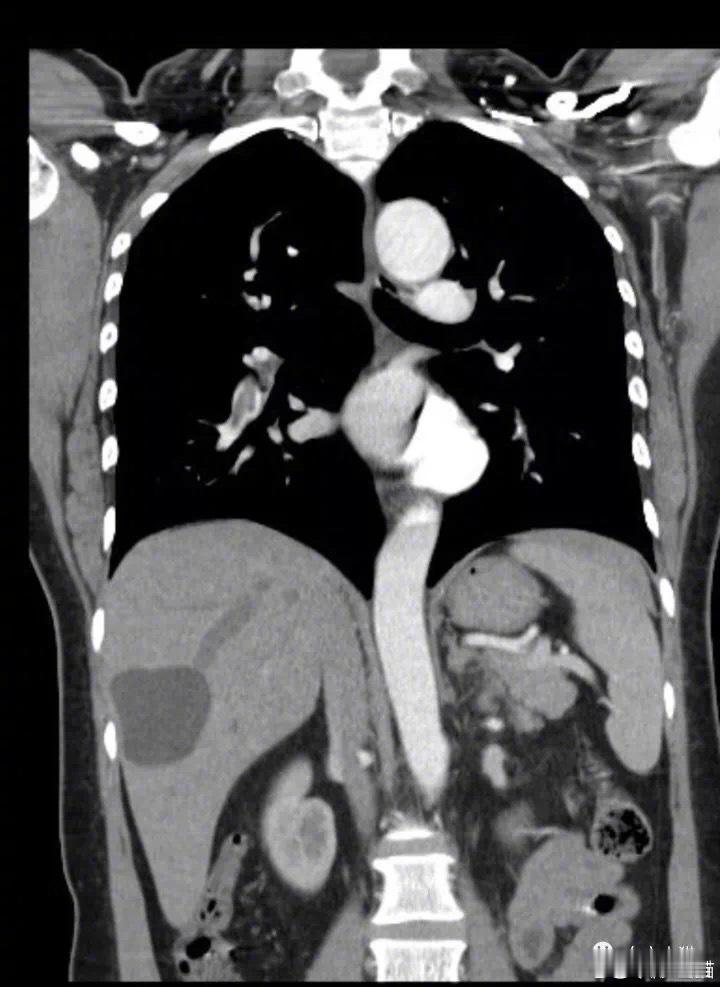

这个时候教授突然想到了,既然病人下腔静脉能够形成血栓,那么病人的肺动脉会不会也能够形成血栓呢?

病人当天的手术停了下来,被推去再次做了个肺部CT。

图片6:患者的左右肺动脉都有血栓形成。

CT结果出来,张教授吓了一跳,患者左右肺动脉都有血栓形成。

如果这个时候给病人做手术,那么由于手术的创伤和手术后血液的高凝状态,肺动脉的血栓形成会加重,如果没有及时发现,肺动脉栓塞出现症状后,患者很难会有生还的机会。

也就是说,她如果在这种情况下动手术,很可能会在手术中或者手术后,因为肺动脉栓塞而死亡。

张教授头上直冒汗,她为自己的小心庆幸不已。